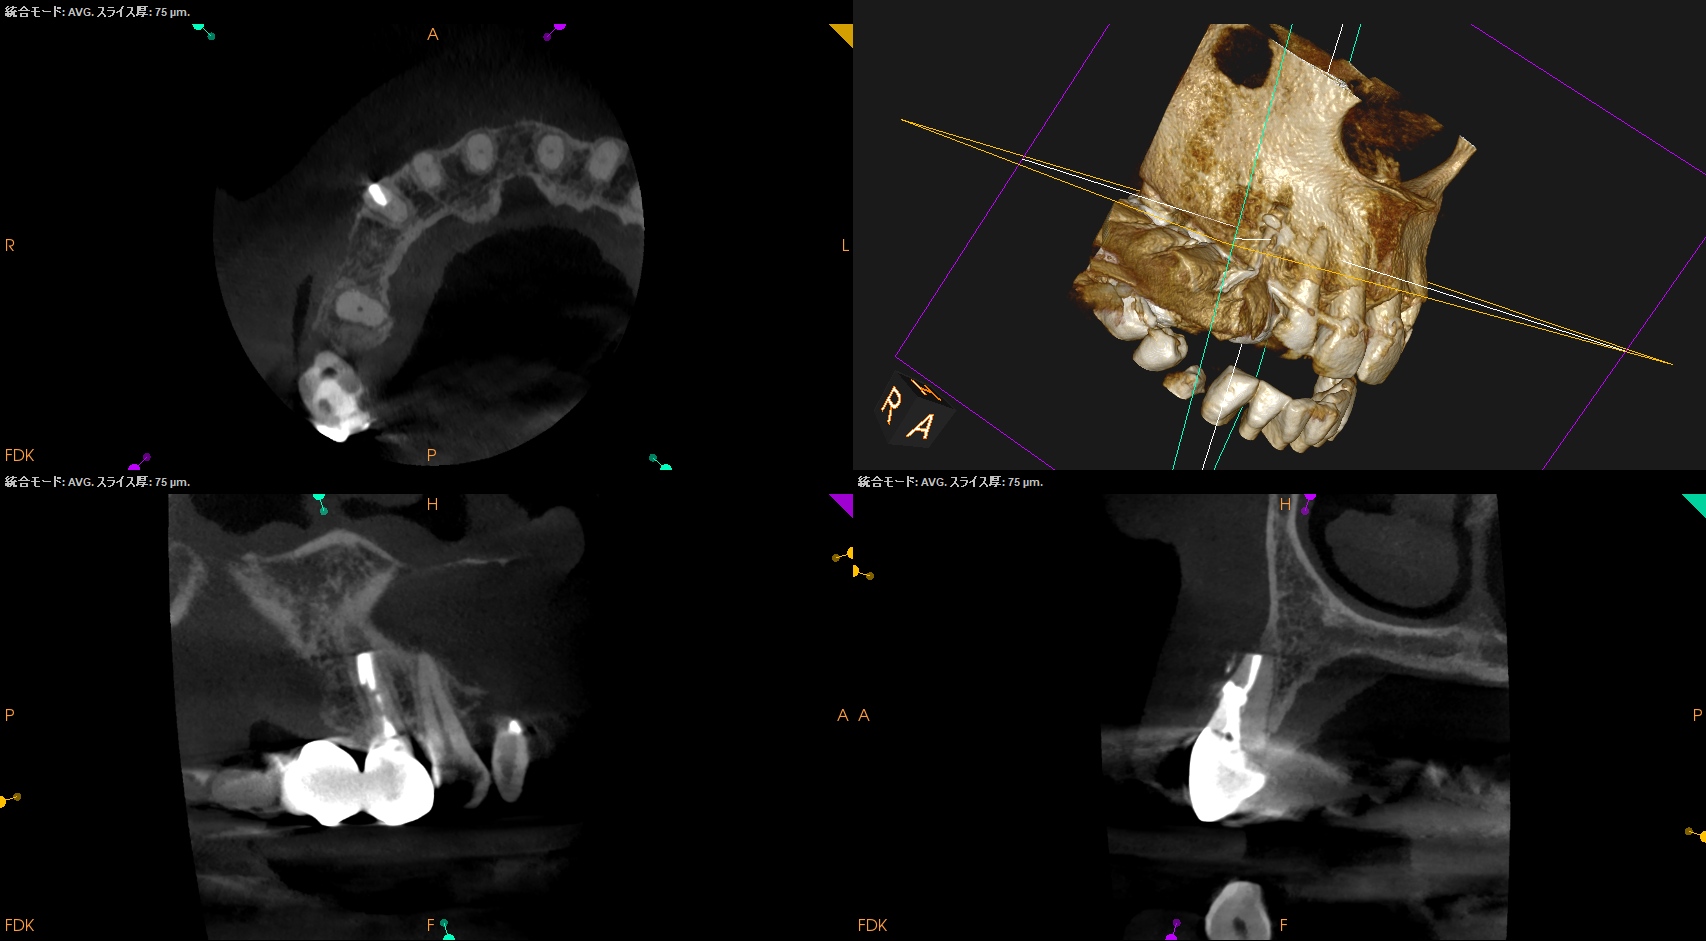

PA, CBCTを撮影した。

しょっぱい逆根管形成になったが主根管は確保されたので縫合して終了した。

#6 Invasive Cervical Root Resorption Repair, Apicoectomy 4M recall(2026.2.13)

根切した部分にはだいぶ骨が添加されているし、外部吸収も進展していないようだ。